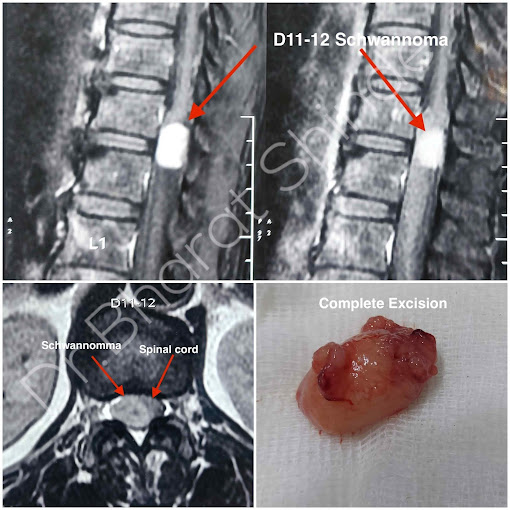

Dr Bharat Shinde completed his M.Ch Neurosurgery from the National Institute Of Mental Health And Neurosciences (NIMHANS), Bangalore which is an institute of National importance.